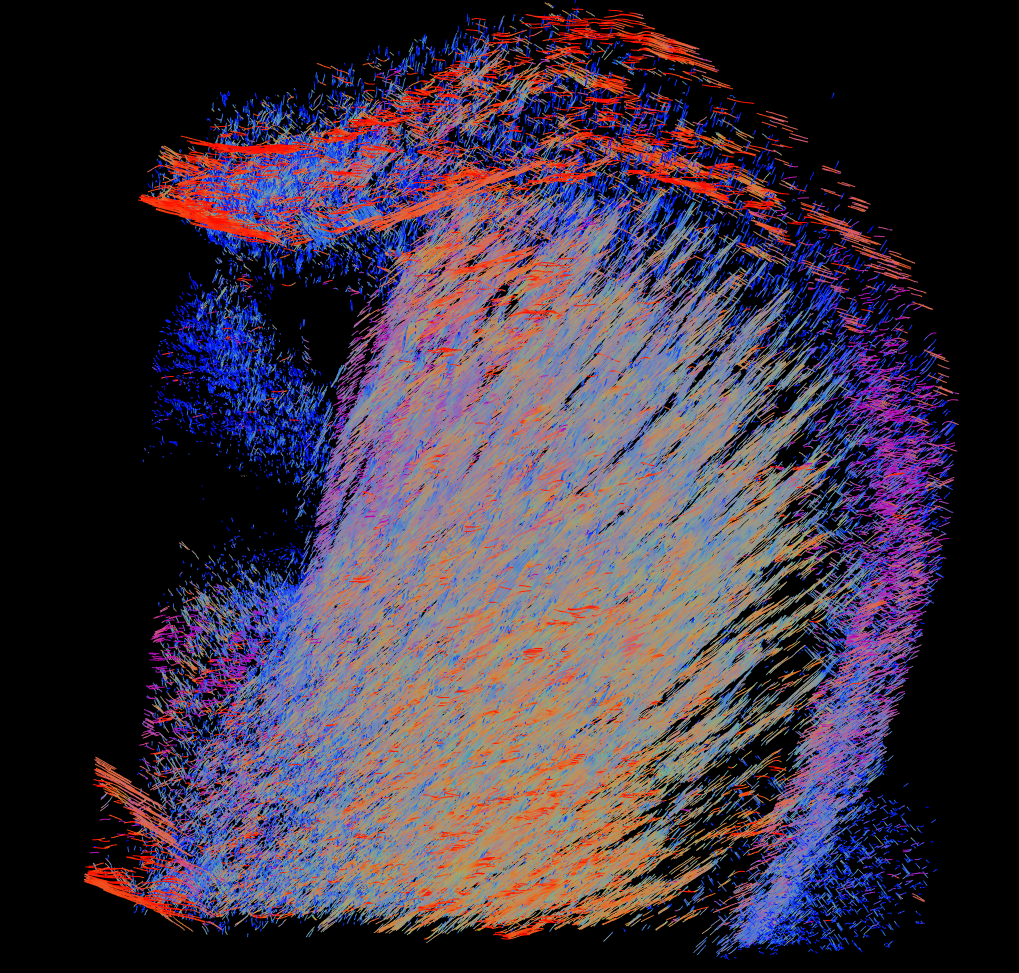

Embarquez pour un voyage immersif à l’intérieur du cerveau ! Entre faisceaux de neurones et vaisseaux sanguins, visualisés en 3 dimensions, découvrez comment une nouvelle méthode d’imagerie médicale contribue à la recherche sur les maladies neurologiques. Les rayons X produits par un accélérateur de particules, le synchrotron, permettent de réaliser une dissection virtuelle, et fournissent de fabuleuses images du cerveau.

© J. Gobé, M. Merabet, E. Brun, F. Chauveau